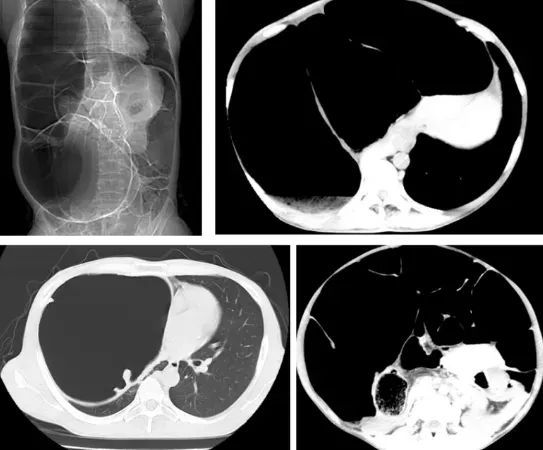

陈女士在哈尔滨医科大学附属第一医院进行CT检查后,医生发现她腹腔内盲肠、升结肠、横结肠、降结肠及部分乙状结肠严重扩张积气,移行段位于乙状结肠,以造成右侧膈肌上移压迫右肺,诊断为特发性巨结肠。

经过腹腔镜微创手术,历时3小时,术中出血量5ml,医生从陈女士体内成功切除60cm长、20cm粗的结肠。医生表示这是十分罕见复杂又巨大的结肠。